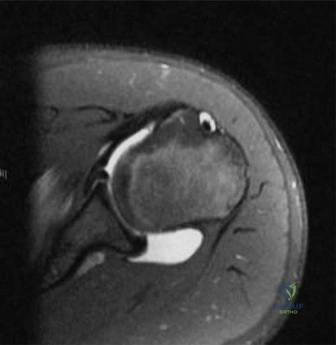

Magnetic resonance imaging is generally reserved for cases where concomitant ligamentous injury is suspected or to evaluate the integrity of the patellar tendon in the setting of a purely cartilaginous patellar sleeve fracture. In this specific presentation, the osseous avulsion is clearly delineated on computed tomography, making magnetic resonance imaging unnecessary for acute surgical decision-making.